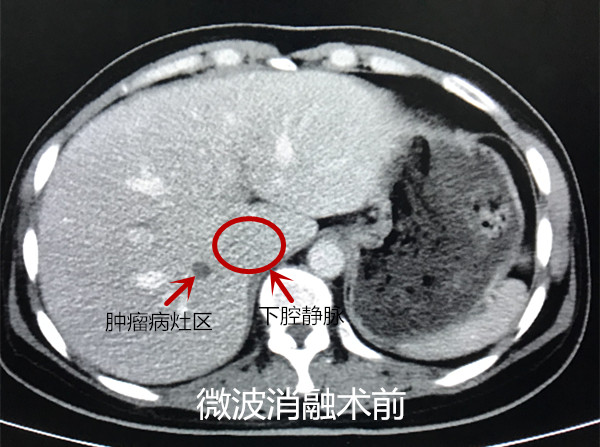

一名46岁的女性结肠癌患者,行肝脏影像学检查发现右肝两枚转移瘤,直径约1厘米,转移瘤的位置比较特殊,一枚位于第二肝门紧邻下腔静脉位置,另一枚位于右肝包膜下紧邻右侧肾上腺。外科意见首先处理肝脏转移瘤,视情况再行结肠肿瘤切除术。

放射科接到会诊通知后立即召开病情讨论会议,考虑到患者肝脏转移瘤体积小,且位置特殊,一枚位于下腔静脉旁、一枚紧邻右侧肾上腺,微波消融治疗难点在于穿刺难、且消融可能造成术中术后肾上腺危象,严重会危及患者生命。王维教授表示介入团队必须要迎难而上,做好术前准备,务必完全灭活肝脏转移瘤,为患者手术切除结肠肿瘤创造必要条件。

在麻醉科的配合下,放射科容鹏飞副教授带领张声旺、吴作为医生于256排CT引导下,精准穿刺、完成两枚肝脏转移瘤微波消融手术治疗,术中、术后患者生命体征稳定,无明显不适,术后血液生化指标基本正常。